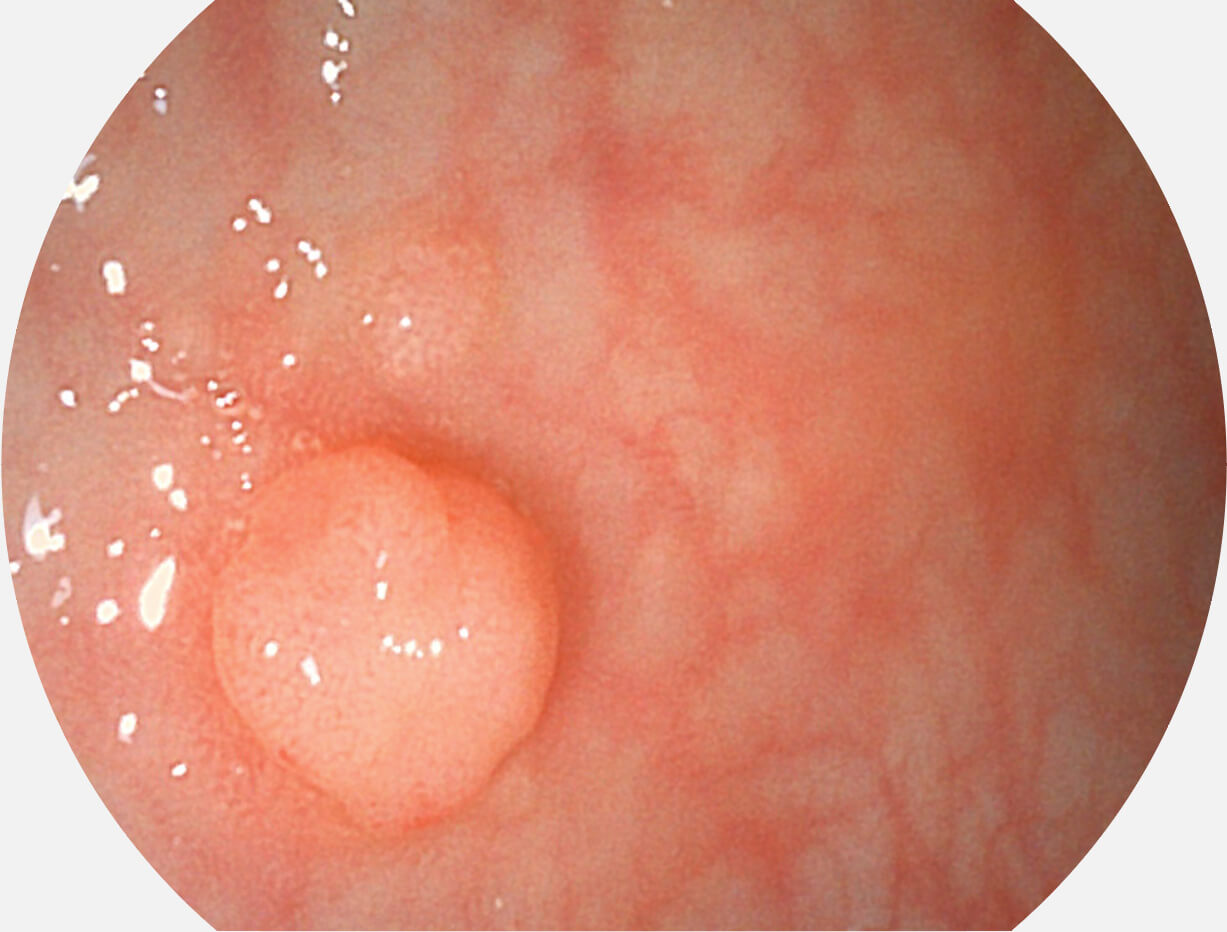

光电复合染色成像技术

Versatile Intelligent Staining Technology, VIST

强调浅层黏膜结构的同时,保证照明亮度和提升浅层微血管与中层血管颜色对比度,病变边界更清晰。

• 白光图像 VIST图像